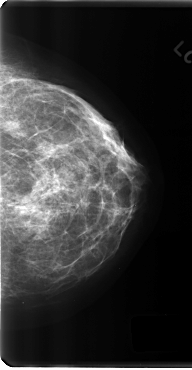

C_0197_1.LEFT_MLO

C_0197_1.LEFT_CC

LEFT_MLO LINES 4696 PIXELS_PER_LINE 2952 BITS_PER_PIXEL 12 RESOLUTION 50 NON_OVERLAY

LEFT_CC LINES 4808 PIXELS_PER_LINE 2496 BITS_PER_PIXEL 12 RESOLUTION 50 NON_OVERLAY